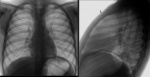

Мальчик 7 лет. Кашляет 2 месяца, пропил 2 курса а/б.

Если бы сам описывал, то написал -норма. А так, может можно привяхаться к головке левого корня и расширению верхнего средостения справа, такое расширение бывает у пожилых - тень ВПВ.

Предполагаю, что ответом окажется инфильтрация в базальном отделе левого легкого, которую можно разглядеть на фоне газового пузыря желудка. Если так, то понимаю, что пропустил бы эту патологию, приняв за скиалогию.

Вы правы. Я тоже пропустила. Прозрела, когда мне показали боковую проекцию.

Тоже не увидел патологию.Вывод: всё мы нарушая стандарт и не делая боковые проекции грудной клетки, "хорошо" пропускаем патологию.